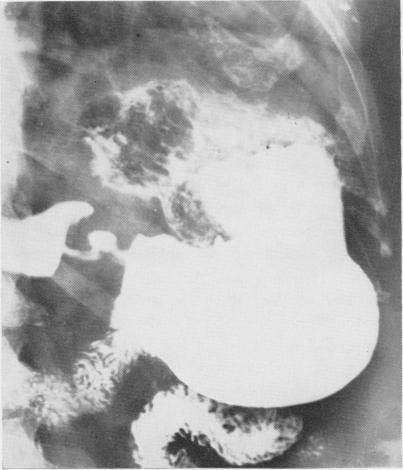

Surgical complications of adrenal steroid therapy.

Ann Surg. 1967 Jun;165(6):1023-34. doi: 10.1097/00000658-196706000-00017.